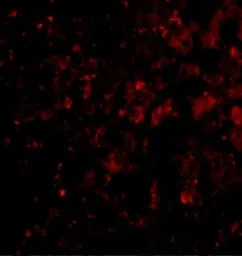

IHC-P analysis of mouse liver tissue using GTX85483 DRAM antibody.

Red : Primary antibody

Blue : DAPI

Dilution : 20 μg/ml